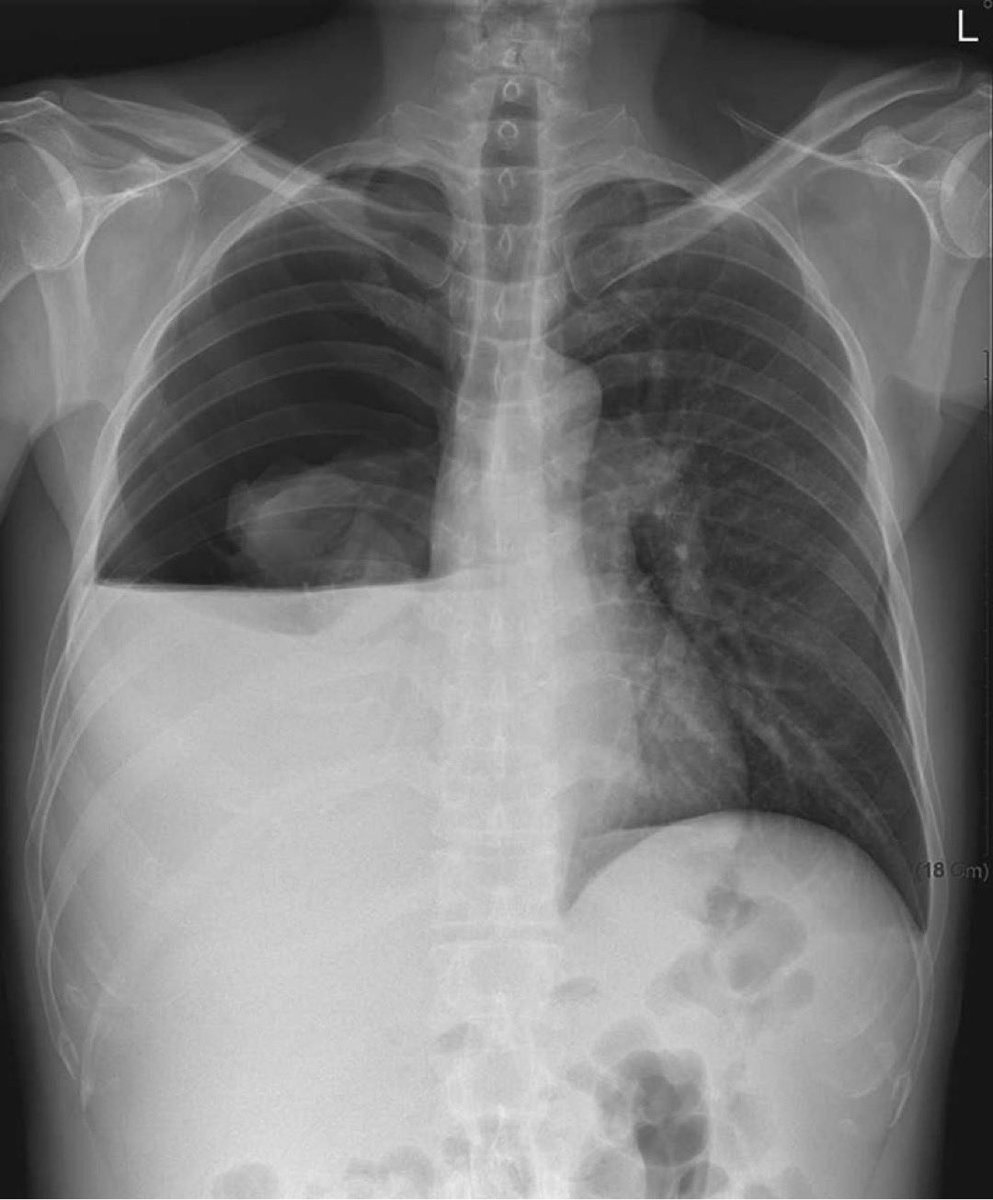

Laura Calderón presented today an interest case of a patient with suspected cardiac sarcoidosis from Buenos Aires Argentina